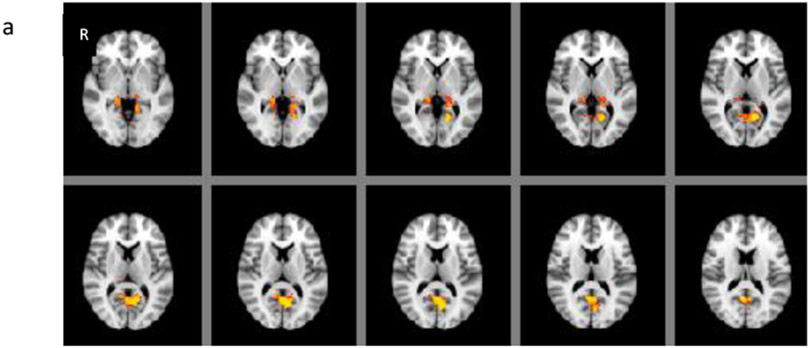

Grey matter volume in CAE was statistically significantly decreased in the areas of right inferior frontal and anterior temporal compared to BECTS and controls (F2, 67 =27.53, p<0.001) (Figures 1a-b). There were no differences between BECTS and controls based on the whole brain voxel-based comparisons. On the other hand, there were statistically significant differences between CAE and controls; grey matter volume was increased in bilateral posterior thalami and in the bilateral inferior precuneus (p < 0.05) (Figure 2a) and decreased in decreased in right inferior anterior frontal, anterior temporal and left posterior medial temporal areas in CAE compared to controls (p < 0.05) (Figure 2b). There was a statistically significant negative correlation with age in various locations in each frontal lobe; superior and anterior frontal in left and inferior lateral frontal in right hemisphere in the control group (r=−0.54, p< 0.05), but not in CAE (r=−0.30) or BECTS (r=−0.12).

Figure 1:

(a) Regions of grey matter volume (blue) including the areas of right inferior frontal and anterior temporal, where statistically significantly decreased in CAE compared to BECTS and controls using ANOVA (F-test). (F 2,67 =27.53, p<0.001). (b) The graph on the right shows each participant (each circle) grey matter volume within all the regions of difference among three groups showing blue in (a).